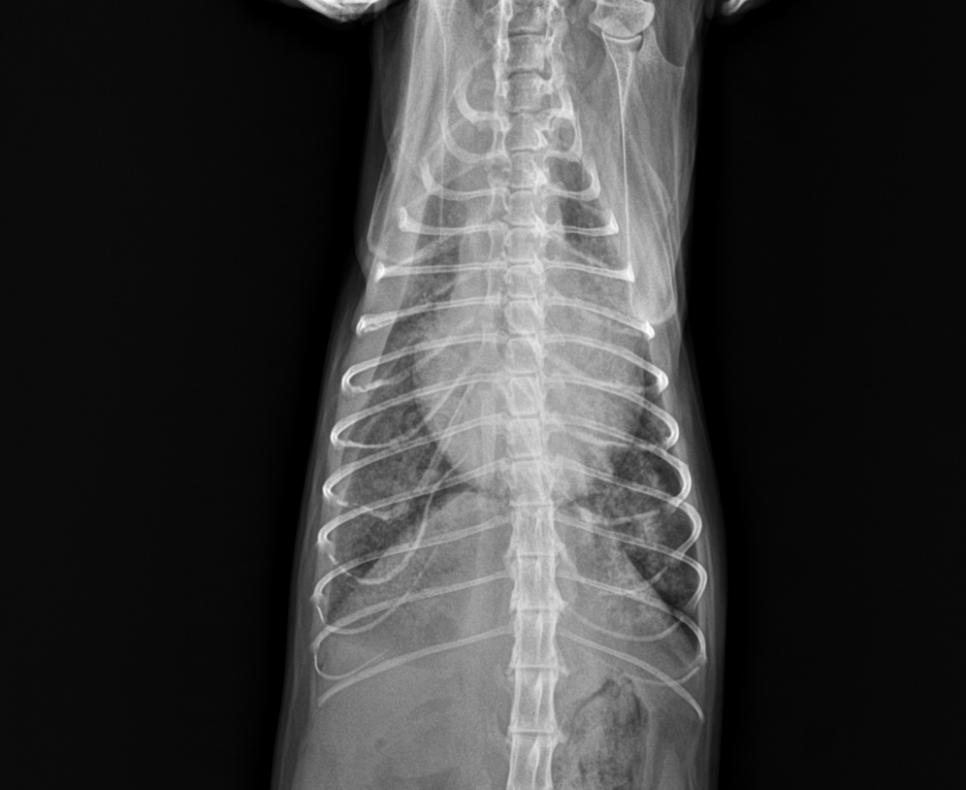

临床检查:精神状态尚可,鼻头湿润,粘膜偏紫,四肢冰凉,四肢脚垫颜色深紫色,耳道皮肤检查无异常,体表淋巴结未见异常,心音异常,肺音正常,眼观腹式呼吸。腹部触诊空虚,BCS3/9,CRT>2S,肛周清洁。

DR显示肺水肿

心脏彩超显示心包积液

全心衰竭

初步诊断

肺动脉高压肺水肿,体循环受阻,为

「心脏衰竭」